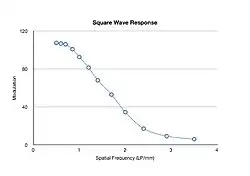

An amplitude profile through an image of the test object allows the modulation at each spatial frequency to be determined - see Figure 6.6 - and can be used to provide more complete information than the limiting resolution on its own.

Here, the modulation is obtained from the difference between the maximum and minimum pixel value at each spatial frequency and expressed in the form of a Square Wave Response (SWR) as shown in Figure 6.7. The modulation is seen to be relatively constant at low spatial frequencies and then to decrease rapidly towards zero. The SWR allows the spatial imaging capabilities to be expressed for both broad, relatively uniform objects, i.e. those with low spatial frequencies, and fine detail, i.e. those with high spatial frequencies, as well as features with intermediate frequencies.